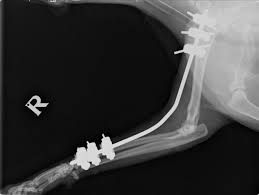

Pin loosening remains one of the most common challenges faced during external skeletal fixation (ESF) in veterinary orthopaed...

Selecting the appropriate fixation method in cats depends on fracture location and pattern, the cat’s overall health, and the sur...

Femoral fractures in cats are challenging injuries that require careful planning. Successful management balances mechanical stability with biological...

Feline femoral fractures are among the most challenging orthopedic injuries in small animal practices. Successful management demands an understanding...

Quadriceps contracture is a challenging but preventable complication in feline orthopaedic practice. It typically develops after femoral fra...